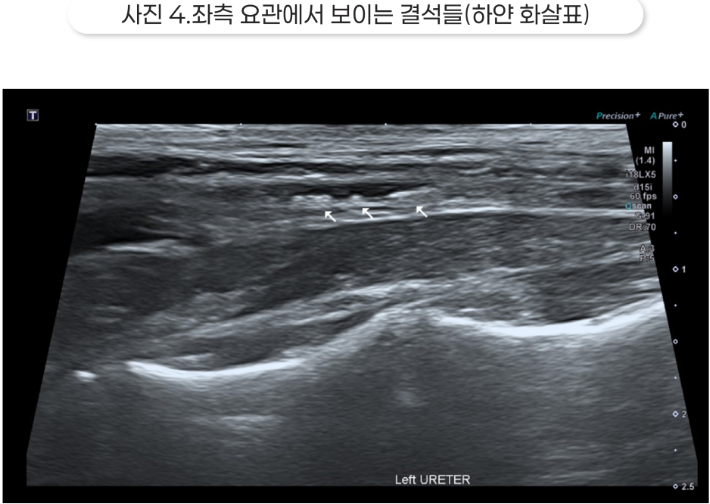

초음파 영상에서는 양측 수신증과 요관 결석이 확인되었습니다.

결석보다 가까운 쪽의 요관은 확장되어 있는데, 이는 요관 폐색을 의미합니다. 신우가 매우 확장되어 있었고, 특히 오른쪽 신장은 피질이 많이 얇아져 있고 심한 수신증 소견을 보였습니다.

수신증이 너무 심하면 해당 신장은 이미 기능을 상실했을 가능성이 높습니다.